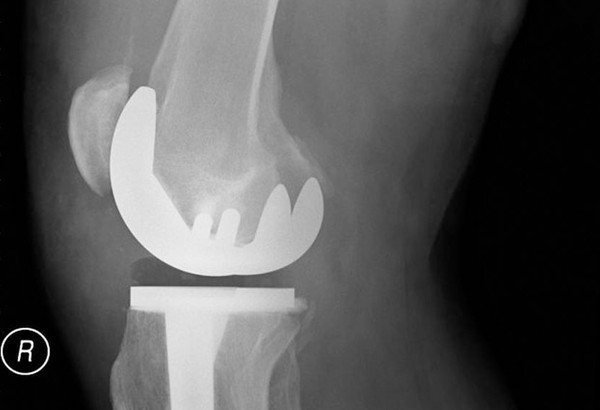

Total Joint Replacement

Patients come to CAO Joint Replacement Physicians seeking long-term relief from arthritis, injury and overuse. We provide the most advanced total joint replacement and revision techniques available so our patients can regain the ability to participate in activities previously limited by pain. Our personal approach to joint replacement and focus on the whole patient are designed to alleviate the anxiety that many patients feel about pursuing treatment for their joint pain.